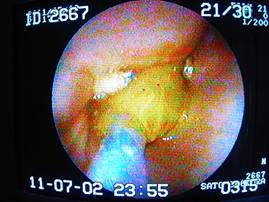

がっちりと鉗子で捕まえ、摘出中。

取り出した異物はこれ。

これは詰まってしまう可能性が充分ありますね。